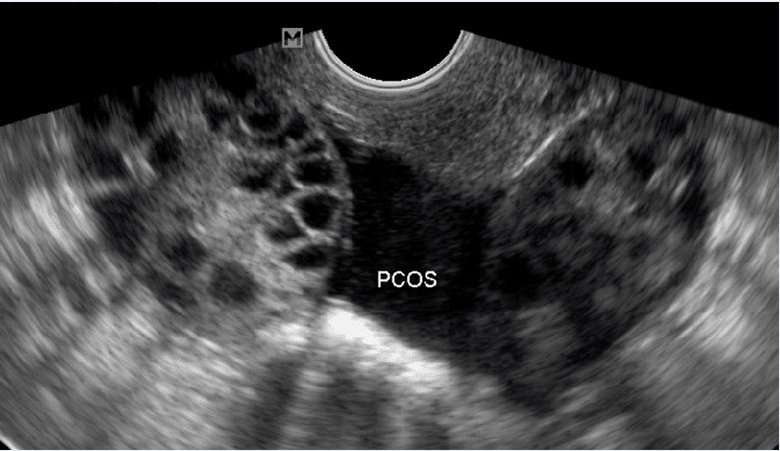

Biểu hiện ban đầu của hội chứng này là kinh nguyệt không đều, thường là dài, số lượng máu kinh ít thất thường. Tuổi dậy thì kéo dài 2-3 năm, sau giai đoạn này kinh nguyệt sẽ đều. Sau vài năm mà vẫn không thấy kinh đều thì có thể đã mắc hội chứng này. Nếu không điều trị gì, 17% trường hợp vẫn có thể mang thai tự nhiên. Số còn lại sẽ diễn biến như sau: Các nang trứng không to lên được, không vỡ được, nằm dưới lớp vỏ dày của buồng trứng. Khi siêu âm, đặc biệt là siêu âm bằng đầu dò qua đường âm đạo, sẽ thấy nhiều nang trứng kích thước dưới 10 mm, phân bố như chuỗi hạt đeo cổ nằm ngay lớp vỏ buồng trứng.